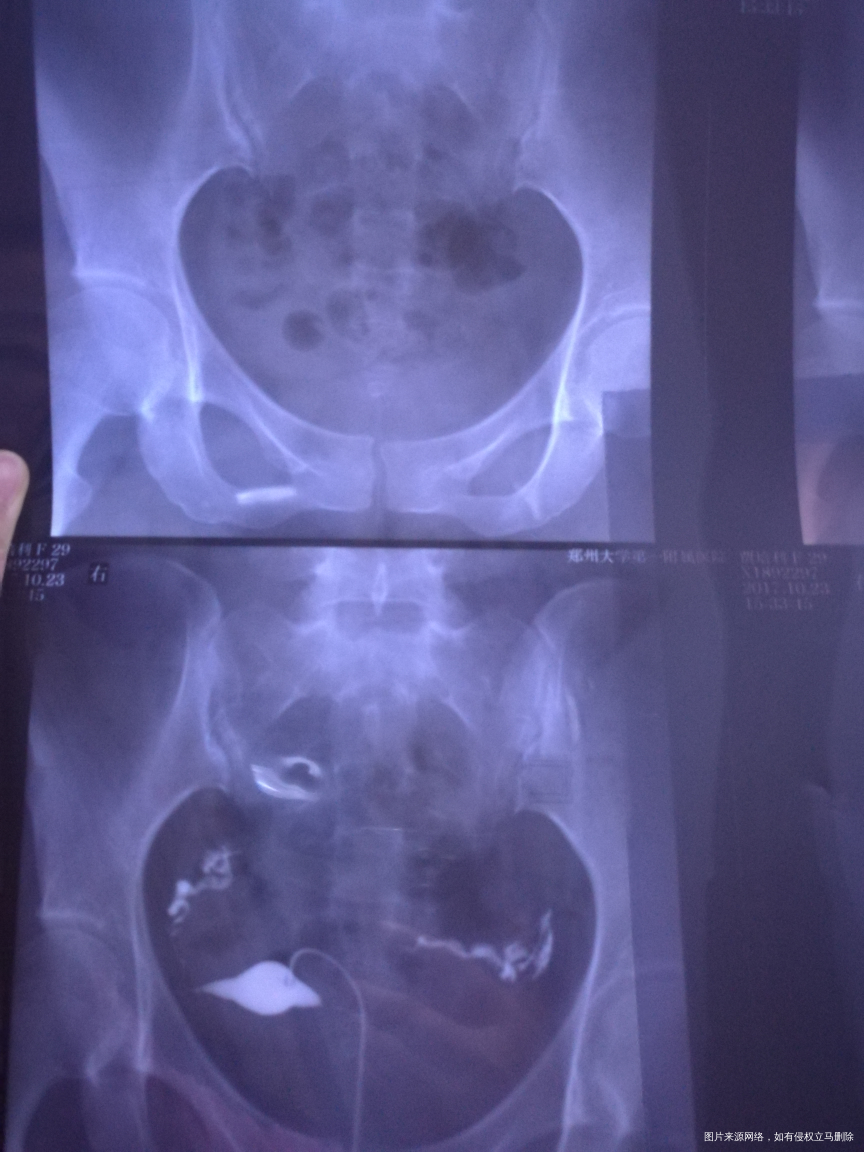

有没有问题,右侧上举严重不???影不影响怀孕?自己备孕两年多了?

您好,双侧输卵管通畅的,可以怀孕试试

天边 回复 赵敏英:右侧是不是有点粘连,上举

考虑盆腔有点粘连可以考虑行腹腔镜手术,建议结合您年龄等综合考虑,祝您好孕,欢迎咨询,满意请点击采纳

你好,输卵管上举是会影响到怀孕的。